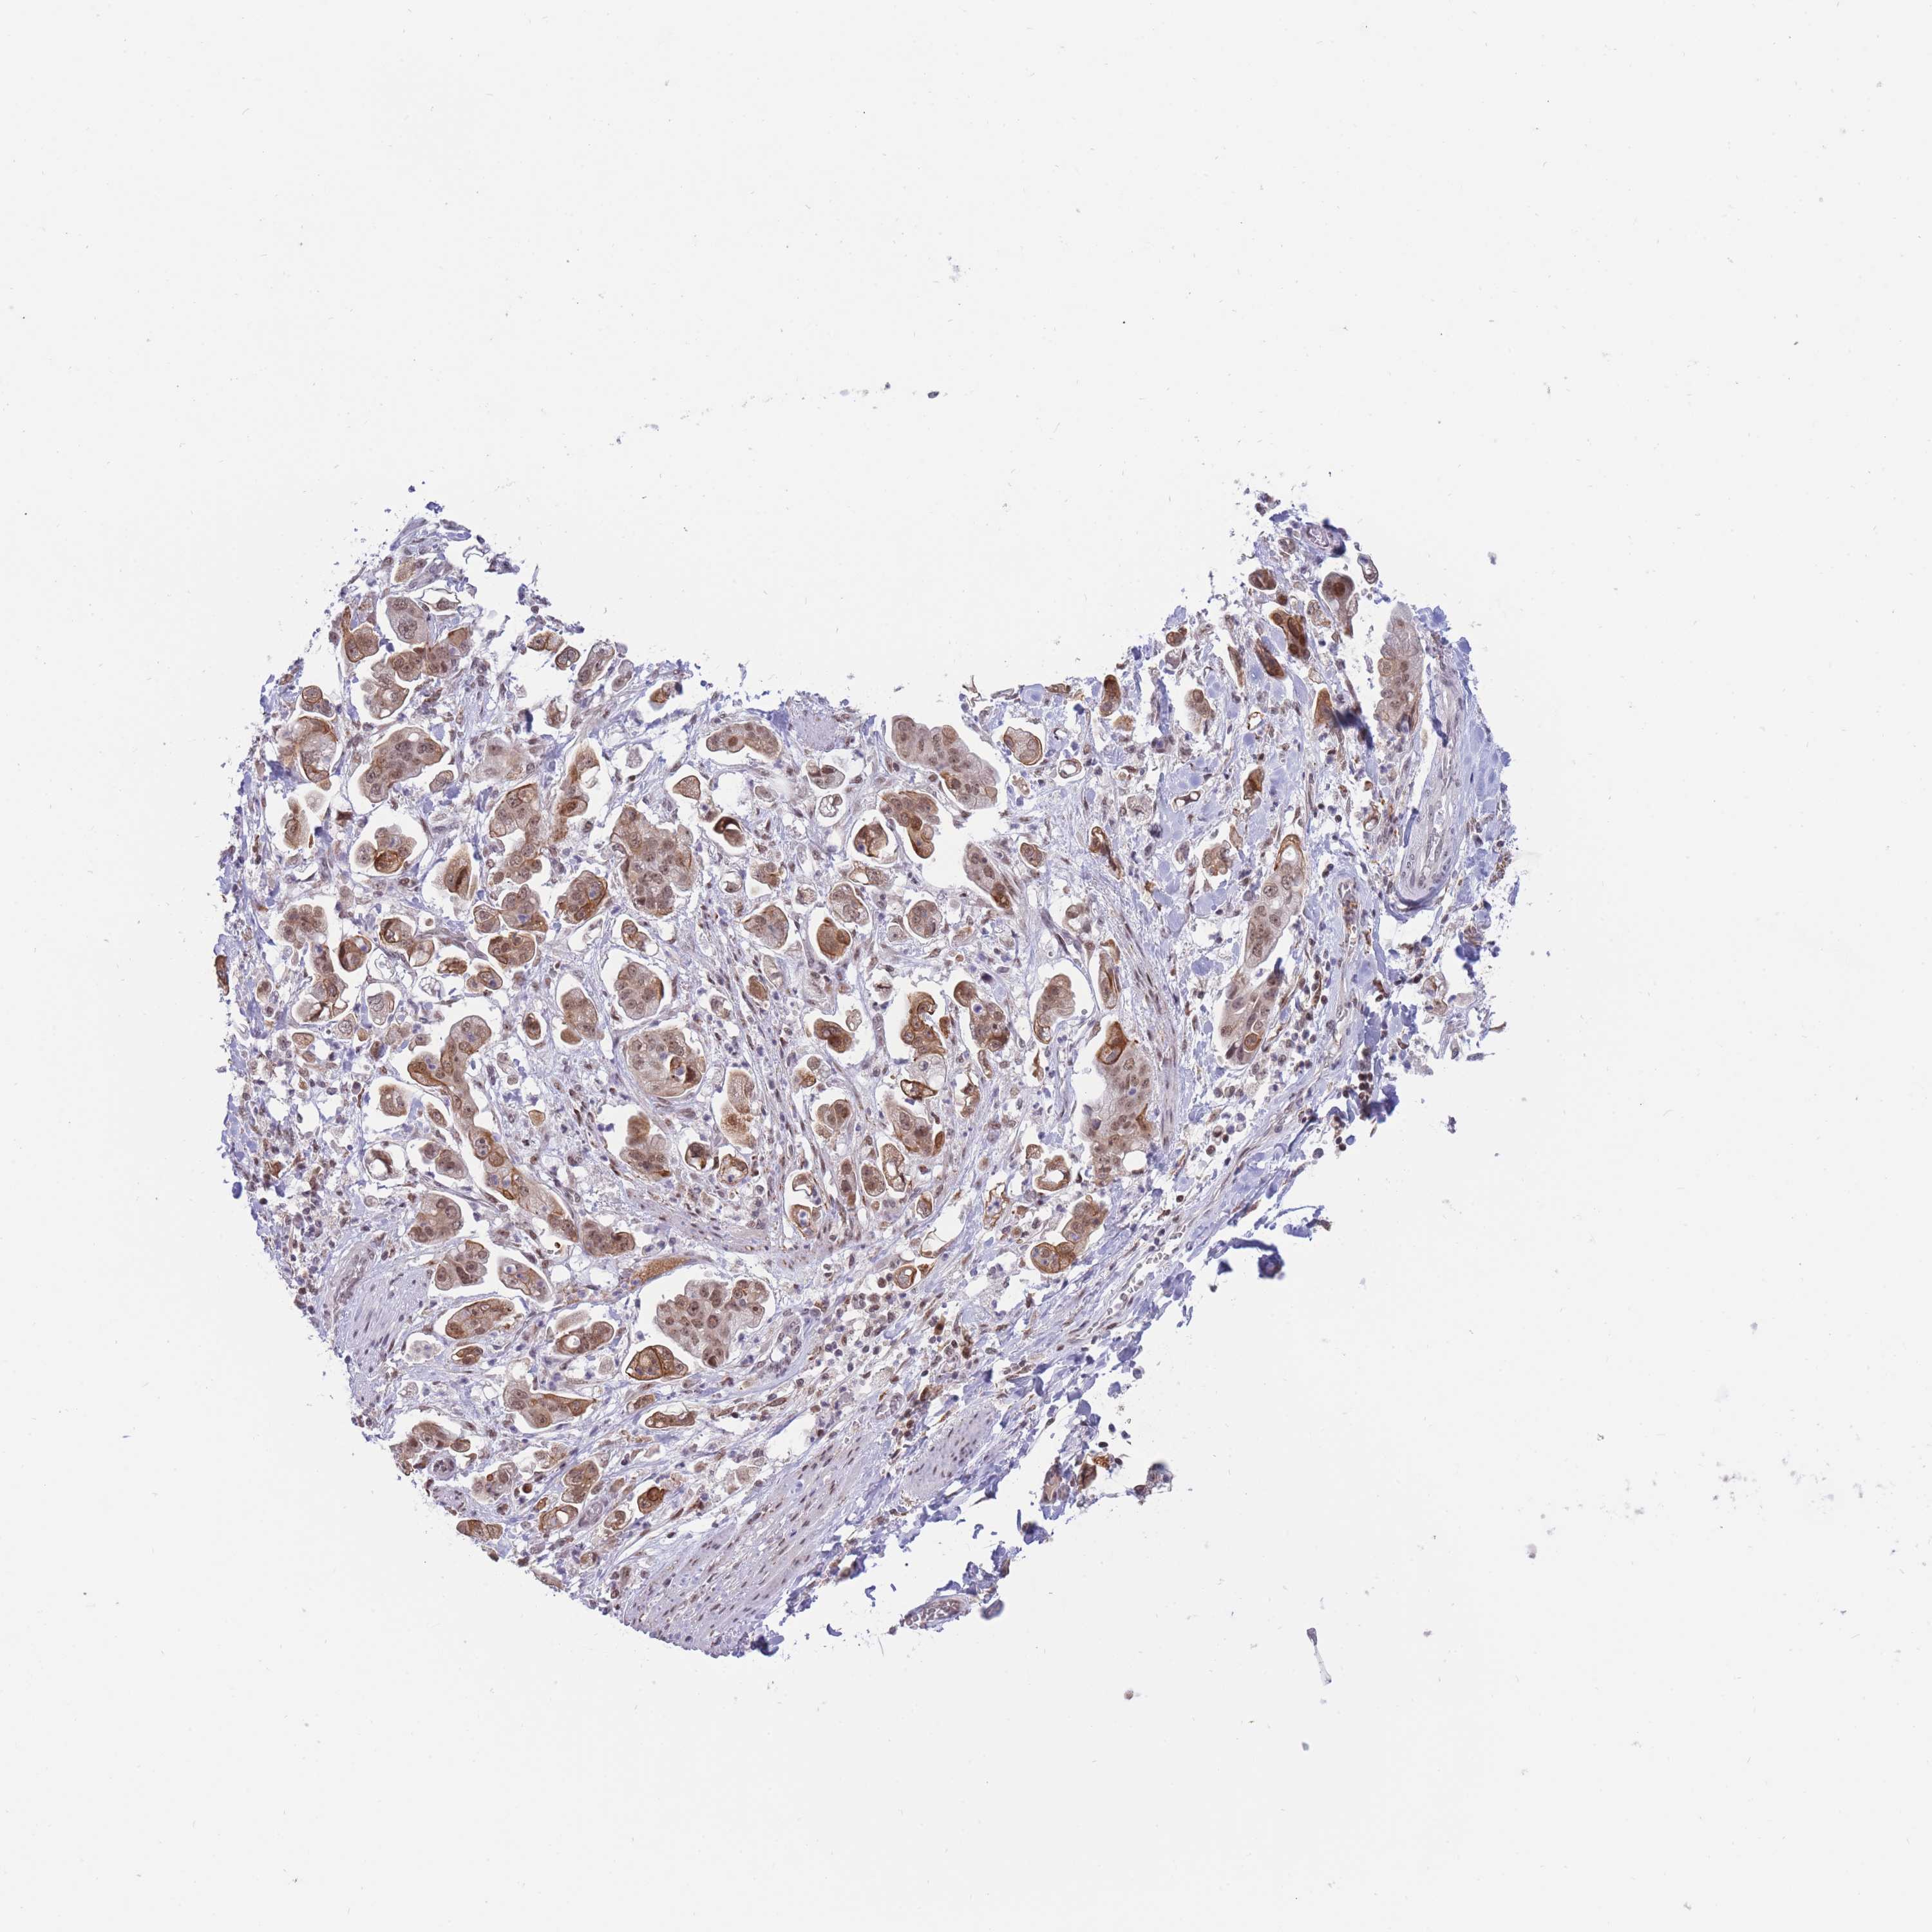

STOMACH CANCER - Protein expressioni

A mouse-over function shows sample information and annotation data. Click on an image to view it in a full screen mode. Samples can be filtered based on level of antibody staining by selecting one or several of the following categories: high, medium, low and not detected. The assay and annotation is described here.

Note that samples used for immunohistochemistry by the Human Protein Atlas do not correspond to samples in the TCGA dataset.

Antibody stainingi

Antibody staining in the annotated cell types in the current human tissue is reported as not detected, low, medium, or high, based on conventional immunohistochemistry profiling in selected tissues. This score is based on the combination of the staining intensity and fraction of stained cells.

Each image is clickable and will lead to virtual microscopy that enables deeper exploration of all samples and also displays staining intensity scores, fraction scores and subcellular localization as well as patient and tissue information for each sample.

Antibody HPA051181

Antibody HPA061454

Antibody CAB069406

Staining

Adenocarcinoma, NOS